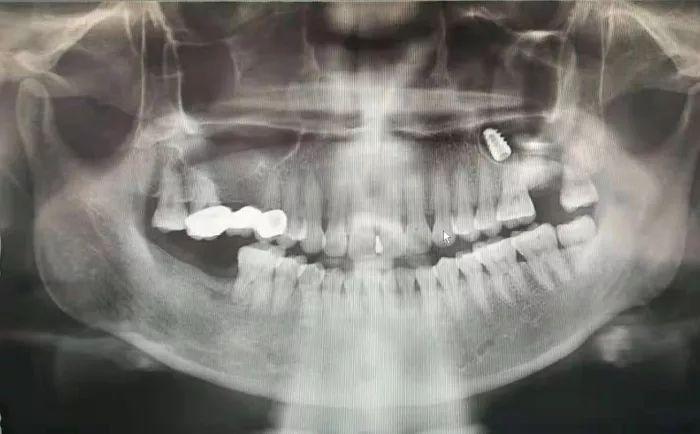

該科副主任崔婧正準(zhǔn)備下班,見狀又忙穿上了白大袿到診室為李先生(化名)進(jìn)行詳細(xì)檢查,影像科馬玉新和陳齊齊醫(yī)生為其拍攝了口腔曲面斷層片發(fā)現(xiàn)其左側(cè)上頜竇內(nèi)有一枚疑似金屬的高密度影像。崔婧仔細(xì)詢問病史后得知,李先生于當(dāng)?shù)啬吃\所做上頜牙齒種植術(shù),卻不慎將種植體捅入了上頜竇,雖然去了多家醫(yī)院卻始終沒能得到有處理。崔婧憑借嫻熟的技術(shù)在局麻下對(duì)患者進(jìn)行上頜竇開窗術(shù),醫(yī)護(hù)人員密切配合,順利取出了上頜竇內(nèi)的種植體。李先生對(duì)醫(yī)務(wù)人員的耐心和的技術(shù)以及拖班后又井然有序的完成急診處理工作表示由衷的感謝。